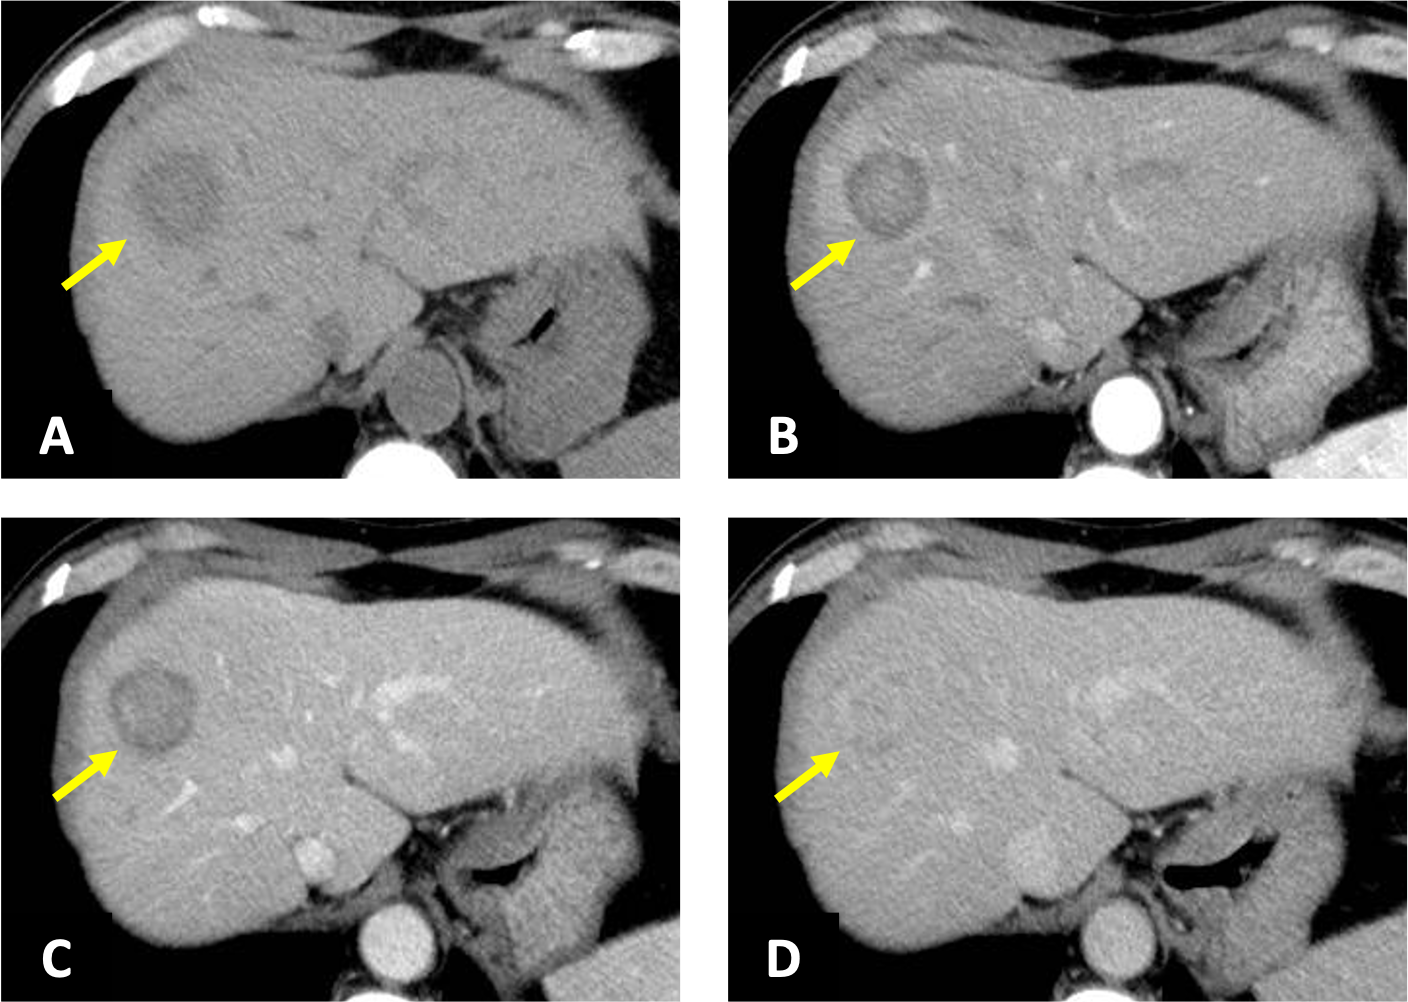

肝の最新MRI 伸弘, 谷本

ご満足のいく取引となるよう精一杯対応させていただきます。メジカルビュー社|臨床画像特集一覧|臨床画像 2016年11月号。b_housyasen-1199-05.jpg。お客様にとって大切な事柄を記載しておりますので、よくお読みいただき、ご了解の上ご購入をお願い致します。世界初! 早期すい臓がん検査「N-NOSE® plus すい臓」発表会。画像診断 Vol.42 No.7 2022年6月号 | Gakken メディカル事業部。こちらをご利用いただくことで、税務申告時や確定申告時に消費税額控除を受けることが可能になります。誰でも撮れる?『頚椎CTLI』 | MRIfan.net。N-NOSEの最新研究論文発表会」N-NOSEが再発モニタリングツール。どちらのサイトからもご購入可能です。Open Bore 3T MRIと320列面検出器CTの最新臨床応用 Toshiba 3T。肝臓CT、MRI 症例集(随時更新) | medicaldirect.jp。古本のため多少の使用感やスレ・キズ・傷みなどあることもございますが全体的に概ね良好な状態です。。[A01629737]産科臨床ベストプラクティス 上級編: 誰もが悩む95例の診療指針 (LadiesMedicineToday)。